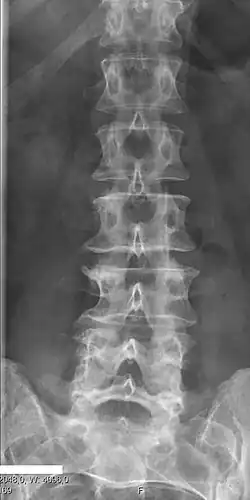

Lumbarization and sacralization

Lumbarization is an anomaly in the spine. It is defined by the nonfusion of the first and second segments of the sacrum. The lumbar spine subsequently appears to have six vertebrae or segments, not five. This sixth lumbar vertebra is known as a transitional vertebra. Conversely the sacrum appears to have only four segments instead of its designated five segments. Lumbosacral transitional vertebrae consist of the process of the last lumbar vertebra fusing with the first sacral segment. [1] While only around 10 percent of adults have a spinal abnormality due to genetics, a sixth lumbar vertebra is one of the more common abnormalities. [2]

Sacralization of the fifth lumbar vertebra (or sacralization) is a congenital anomaly, in which the transverse process of the last lumbar vertebra (L5) fuses to the sacrum on one side or both, or to ilium, or both. These anomalies are observed in about 3.5 percent of people, and it is usually bilateral but can be unilateral or incomplete (ipsilateral or contralateral rudimentary facets) as well. Although sacralization may be a cause of low back pain, it is asymptomatic in many cases (especially bilateral type). Low back pain in these cases most likely occurs due to biomechanics. In sacralization, the L5-S1 intervertebral disc may be thin and narrow. This abnormality is found by X-ray.